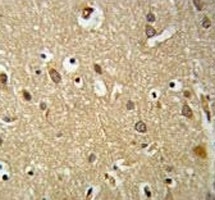

Supportive validation

- Submitted by

- NSJ Bioreagents (provider)

- Main image

- Experimental details

- IGF1R antibody IHC analysis in formalin fixed and paraffin embedded brain tissue.